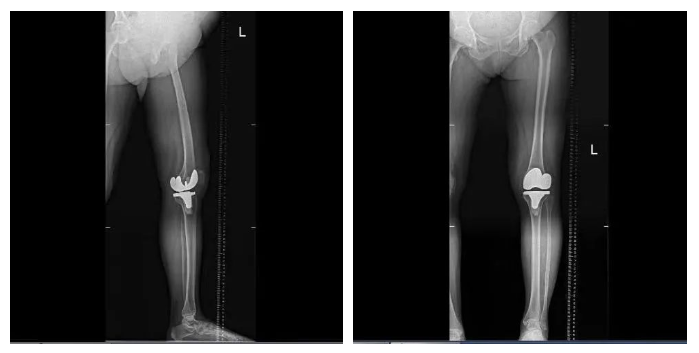

手術(shù)全程操作流暢高效,通過(guò)術(shù)后測(cè)量顯示,實(shí)際截骨量、術(shù)后下肢力線與術(shù)前規(guī)劃完全一致,真正實(shí)現(xiàn)了高效和精準(zhǔn)。此外,鴻鵠?的自動(dòng)定位截骨功能,避免了傳統(tǒng)手術(shù)中采用髓內(nèi)定位工具可能會(huì)對(duì)患者髓腔造成一定損傷等問(wèn)題,很大程度減少了軟組織和骨組織的損傷,患者出血少、創(chuàng)傷小,術(shù)后膝關(guān)節(jié)功能的康復(fù)更快。據(jù)悉,患者術(shù)后恢復(fù)良好,第二天即可進(jìn)行早期功能鍛煉。

▲患者術(shù)后平片